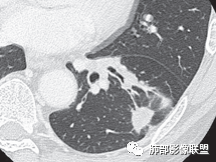

三、影像表现:左肺上叶多发片状高密度影,散在,边缘模糊,支气管壁稍增厚,中轴间质、小叶间隔增厚、有结节感,左肺上叶前段病灶可见胸膜增厚,部分小支气管不能分辨;右肺上叶后段混合磨玻璃结节,边界清,邻近胸膜凹陷;纵膈淋巴结肿大;心包增厚;左侧少量胸水。此外,扫及右侧胸腔内甲状腺肿;左侧肩胛骨旁肌群内脂肪瘤。

四、综合分析:老年男性,以咳嗽咳痰为主要临床表现,无发热,白细胞正常,影像表现为左肺上叶片影,前段结节影、胸膜增厚、部分小支气管不能分辨。左肺上叶中轴间质增厚、小叶间隔增厚、结节感,肺门纵隔见肿大淋巴结,尽管肺部病病灶边缘特征不典型,但高度疑及癌性淋巴管炎这一“次生灾害”却具有相当重要提示意义,而肺癌中最常伴癌淋的就包括腺癌。右肺上叶后段混合磨玻璃结节,边界清楚,张力明显,具有一定特征性,高度指向浸润性腺癌。这对于左肺病灶具有一定程度“助攻”效应。总体而言,本例左肺病灶的诊断关键点在于判断出癌性淋巴管炎。癌性淋巴管炎的结节在外围间质多见,小叶间隔可呈串珠状、结节状增厚,由于出血及水肿,小叶间隔增厚较明显,或呈不规则增厚。有的肺小叶呈多角状阵列。常合并胸水。